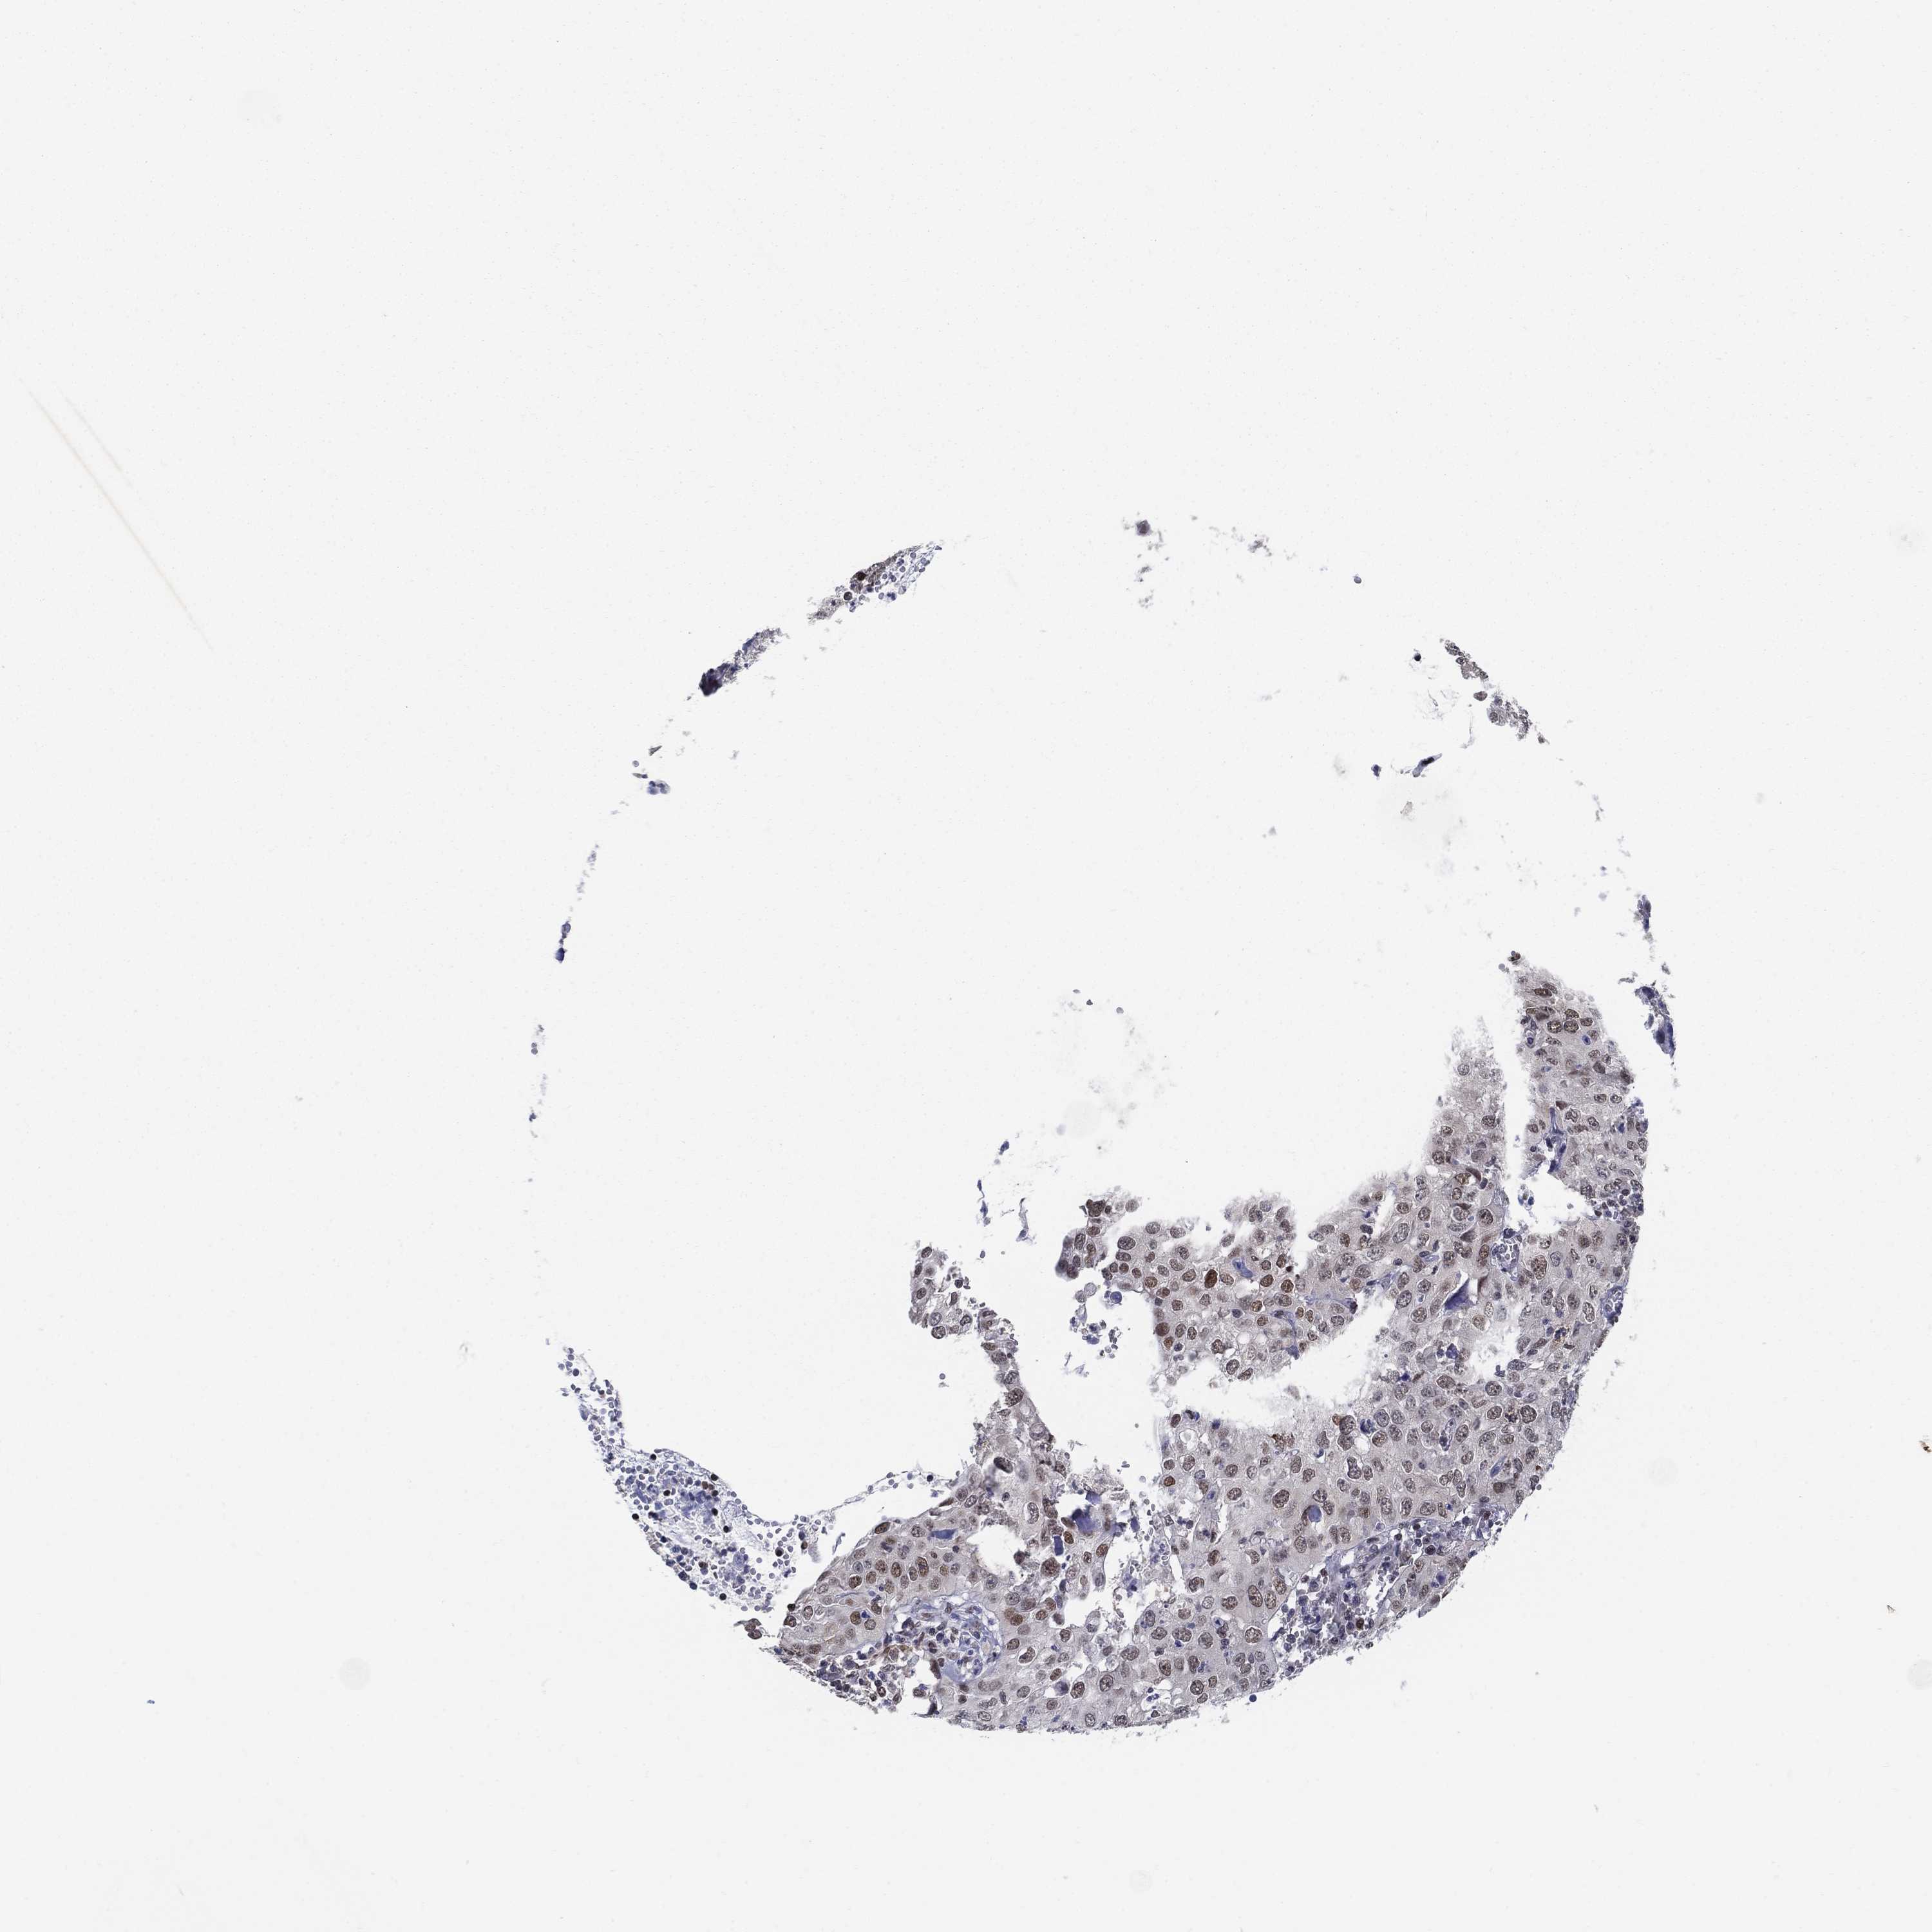

CERVICAL CANCER - Protein expressioni

A mouse-over function shows sample information and annotation data. Click on an image to view it in a full screen mode. Samples can be filtered based on level of antibody staining by selecting one or several of the following categories: high, medium, low and not detected. The assay and annotation is described here.

Note that samples used for immunohistochemistry by the Human Protein Atlas do not correspond to samples in the TCGA dataset.

Antibody stainingi

Antibody staining in the annotated cell types in the current human tissue is reported as not detected, low, medium, or high, based on conventional immunohistochemistry profiling in selected tissues. This score is based on the combination of the staining intensity and fraction of stained cells.

Each image is clickable and will lead to virtual microscopy that enables deeper exploration of all samples and also displays staining intensity scores, fraction scores and subcellular localization as well as patient and tissue information for each sample.

Antibody HPA042294

Staining

High

Medium

Low

Not detected

Intensity

Strong

Moderate

Weak

Negative

Quantity

>75%

75%-25%

<25%

None

Location

Nuclear

Cytoplasmic/membranous

Cytoplasmic/membranous,nuclear

Squamous cell carcinoma, NOS

Adenocarcinoma, NOS